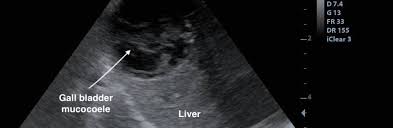

When seen signs include vomiting jaundice loss of appetite abdominal pain and fever. So after much research I want to share what Ive learned through my vet the ultrasound radiologist and the best medical sources of information on the Internet about gallstones gallbladder and bile duct inflammation in cats.